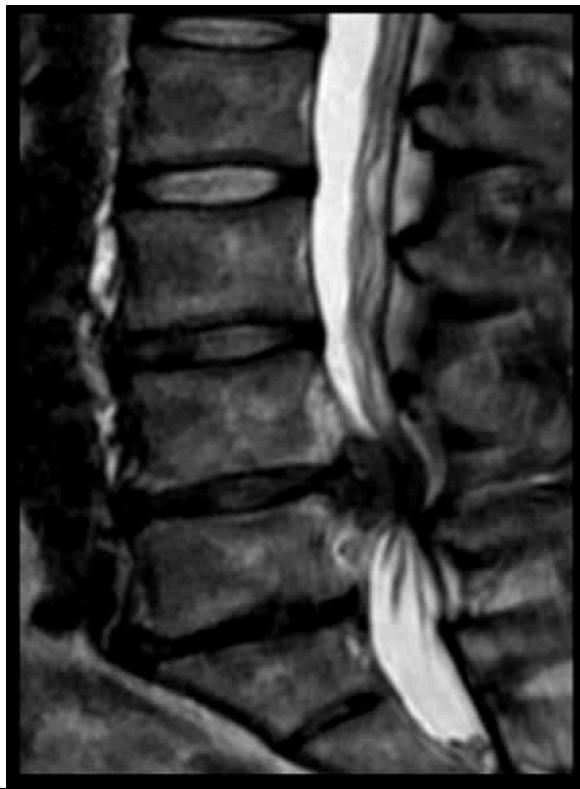

Cauda Equina SyndromeZ

- Etiology: Severe compression of nerve roots in the thecal sac of lumbar spine, most commonly due to acute lumbar disc herniation

- Critical: Early diagnosis is essential

Clinical Features:

- Back pain (most common)

- Unilateral or bilateral leg pain (2nd most common)

- Saddle anesthesia (highly specific)

- Bladder dysfunction: Urinary retention → overflow incontinence

- Unilateral or bilateral sensory changes in legs

- Unilateral or bilateral motor weakness in legs

Diagnosis:

- Urgent MRI to confirm cause

Treatment:

- Prompt surgical decompression

- Should be performed within 24 hours, absolutely within 48 hours